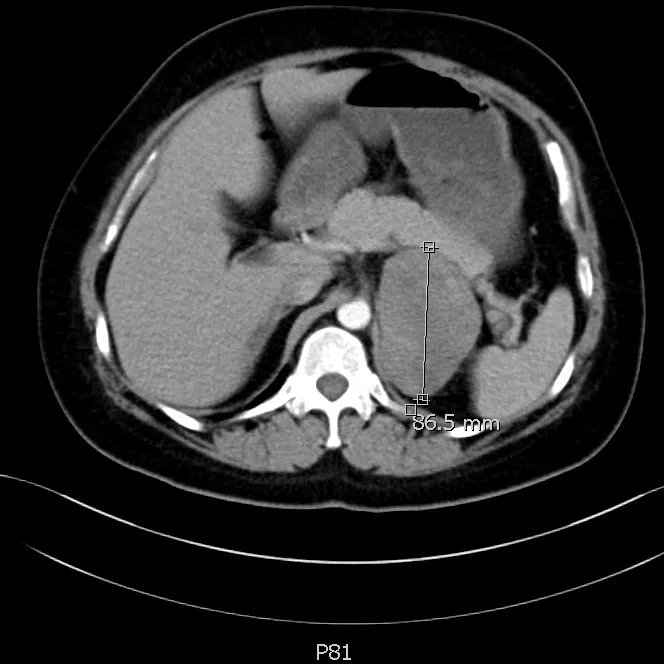

追问病史,患者坦言近一年体貌变化显著,体重明显增加,血压增高,且伴随持续性疲劳、阵发性多汗、心悸等症状。进一步的肾上腺功能检测显示,她的皮质醇、雄激素等关键指标显著异常。结合增强CT显示的肿瘤体积巨大、内部密度不均、强化不均匀等影像学特征,杨国胜诊断顾女士极可能是罕见的肾上腺皮质癌(Adrenocortical Carcinoma, ACC)。

▲肾上腺增强CT结果